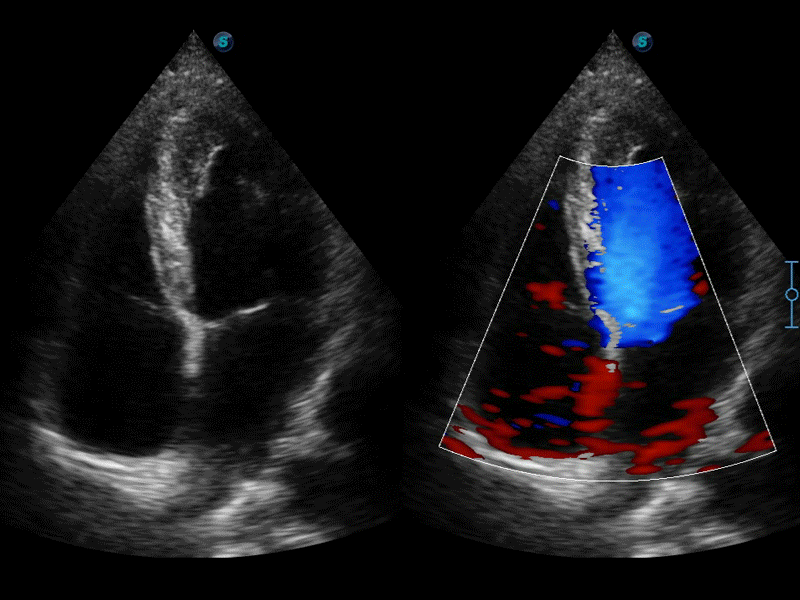

高分辨率血流成像技術(shù)提高了對低速血流信號的檢測能力。在提高空間分辨率的同時,也克服了血流外溢現(xiàn)象,為用戶提供更加真實的血流動力學(xué)信息。